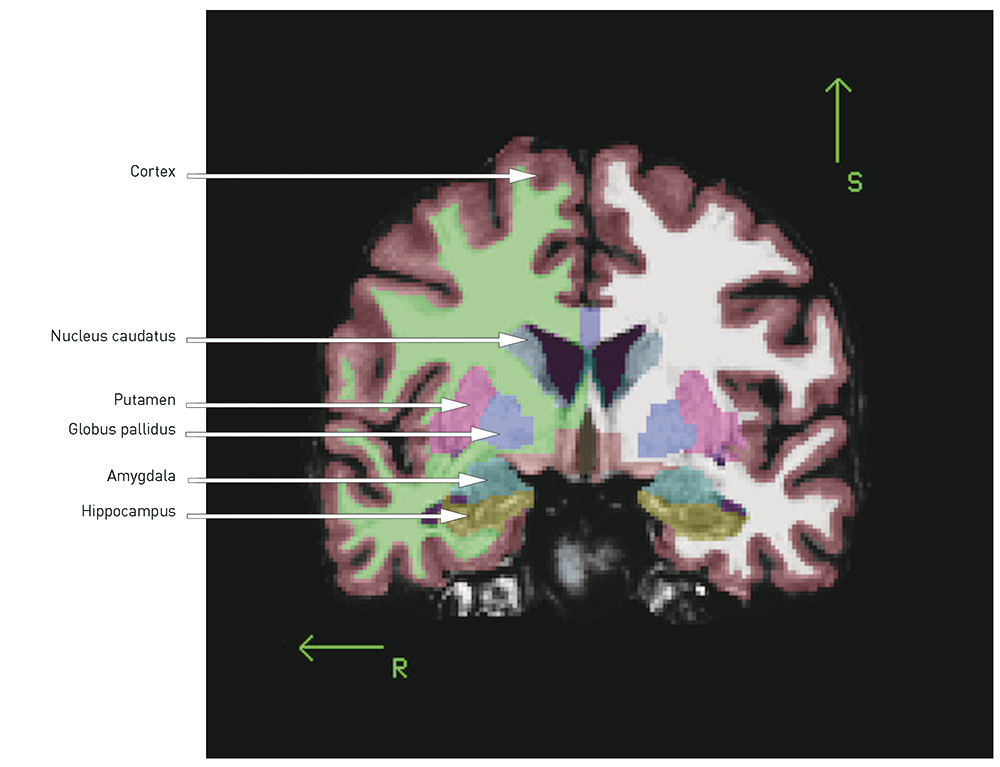

When the total volume is smaller and the ventricles enlarged, the question is whether there are certain regions or structures where the volume reduction is more pronounced. The following is a brief review of the best replicated findings (for illustration, see Figs. 1 and 2):

Fig. 2  Three-dimensional illustration of subcortical structures based on a template from the MRI post-processing tool…

Fig. 2 Three-dimensional illustration of subcortical structures based on a template from the MRI post-processing tool FreeSurfer. Illustration © Ørjan Bergmann

The hippocampus is located medially in the temporal lobe of the brain and is important for verbal learning and memory. It is generally reported to be smaller in patients with schizophrenia than in healthy control subjects (4, 9), a finding we have also reported from two Scandinavian cohorts (7, 11, 12). In a recently published meta-analysis of 44 MRI studies, the effect size was found to be medium (d = – 0.48 and – 0.53 for the left and right hippocampus respectively) (13), and there was no difference between first-episode and chronic schizophrenia. That the changes were present at onset of the illness may indicate that the hippocampal volume reduction in schizophrenia is developmentally related. The hippocampal volume reduction may represent a loss of grey matter, which may be significant for cognitive functions like learning and memory, which have been shown to be impaired in schizophrenia (14).

A number of studies, including our own (7, 11, 15), as well as several meta-analyses (5, 16, 17), have demonstrated in cases of schizophrenia an enlarged volume of the basal ganglia, especially pronounced in the globus pallidus. The basal ganglia are rich in dopamine fibres, and changes may therefore be difficult to interpret since the structures are affected by antidopaminergic antipsychotics (18).

The thalamus, a mid-line structure that borders on the ventricles, has proved to be smaller in patients with schizophrenia (19). In one meta-analysis, an effect size has been found of d = – 0.32 (right) and d = – 0.33 (left) in chronic schizophrenia and d = – 0.45 (right) and d = – 0.48 (left) in first-episode schizophrenia (20). The thalamus functions as a key node in the brain’s cognitive processes, and one hypothesis is that the flow of information between different areas of the brain is disrupted in schizophrenia (21).

The cortex is a complex structure with sulci and gyri. The neurons in the cortex are among other things involved in volitionally controlled and complex cognitive processes. The first MRI studies found a smaller cortical volume, particularly in the frontal and temporal lobes (4). This volume loss has been replicated in a number of later studies and may reflect a reduction of neuropil (unmyelinated nerve cells, synapses and glial cells), as has been found in neuropathological post mortem studies of schizophrenia patients (22). A smaller volume may be caused by a reduction in thickness and/or area (volume = thickness x area). In our group’s study from Oslo, we found a thinner cortex and a smaller area and volume in schizophrenia, where the changes in volume were «driven» by the reduction in thickness (23). This finding is consistent with several other studies that show a thinner cortex, most pronounced in the frontal and temporal areas, in schizophrenia (24) – (26).